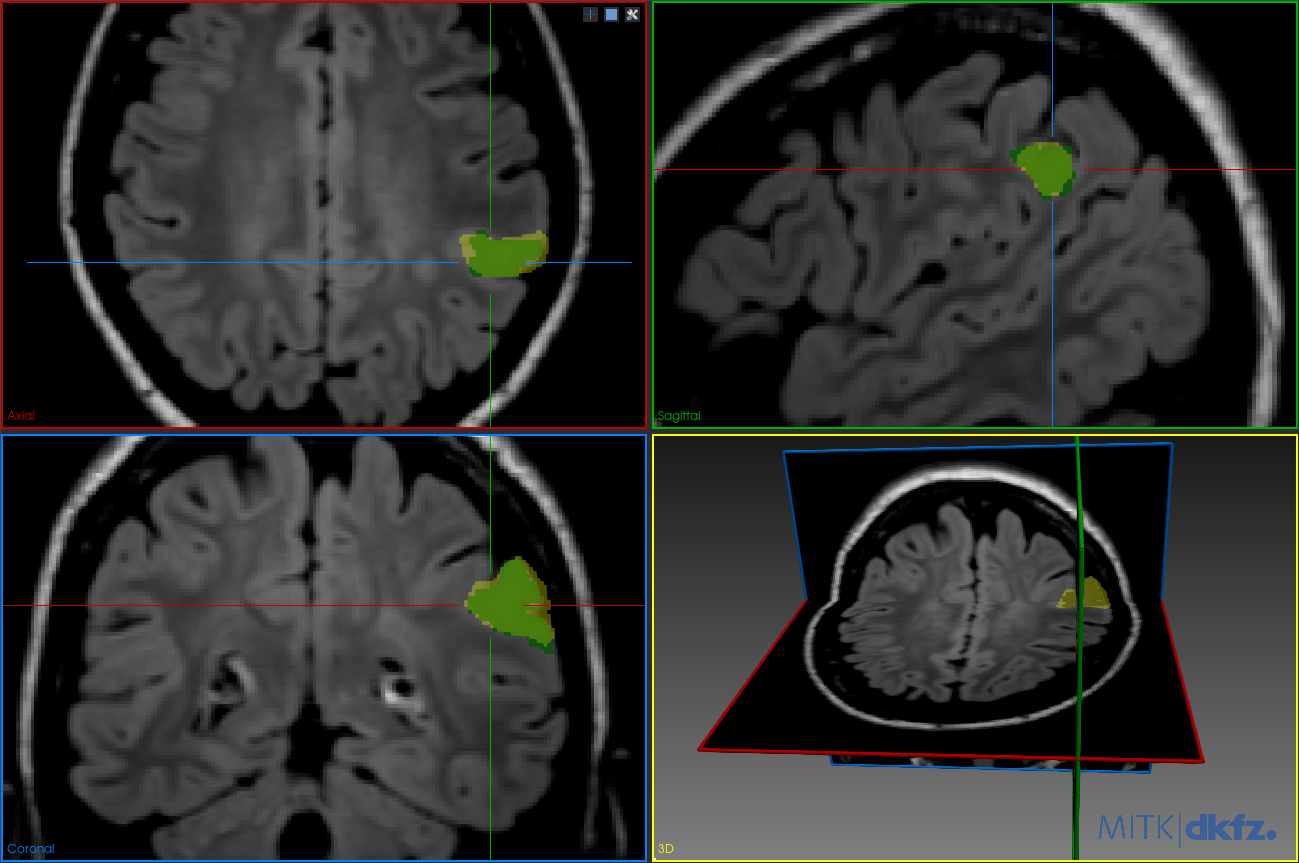

We visualize the segmentation results on a representative test subject to illustrate the effect of post-processing and the contribution of including TV loss during training (Figure 2 and Figure 3). Visualizations were generated using the MITK software333https://github.com/MITK/MITK. Figure 2 illustrates the segmentation results produced by the base model trained only with Dice Loss, before and after applying post-processing. In Figure 2(a), we can see a false positive cluster in the predicted mask (blue) that does not overlap with the ground truth (green), indicating a lack of spatial consistency in the raw network output. In Figure 2(b), after post-processing, the false positive cluster is successfully removed (yellow mask), confirming that connected component analysis can enforce smoother predictions as a post hoc fix.

Refer to caption

(a) Results of the base model. Green: ground truth mask; blue: predicted mask. Note the false positive cluster in the axial view (top-right pane).

(b) Results after applying post-processing. Green: ground truth mask; yellow: predicted mask. Note that the false detection is removed.

Figure 2: Comparison of predicted segmentation before and after post-processing for the base model.